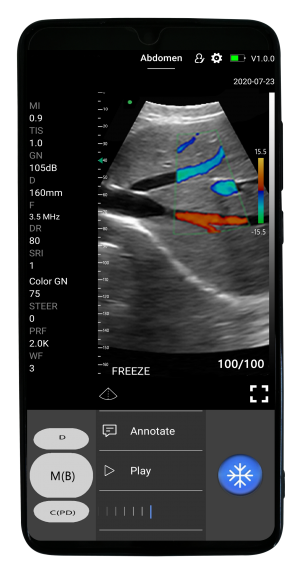

D5CL

El escáner de ultrasonido portátil de doble sonda es una solución avanzada diseñada para ofrecer máxima versatilidad clínica en un solo dispositivo. Gracias a su tecnología integrada, combina tres modos de escaneo —convexo, lineal y phased array— permitiendo evaluar estructuras profundas, tejidos superficiales y realizar estudios cardíacos con alta precisión. Esta integración reduce significativamente los costos al reemplazar la necesidad de adquirir múltiples sondas por separado.

Su diseño compacto y liviano lo convierte en una herramienta ideal para emergencias, rondas hospitalarias, clínicas comunitarias y evaluaciones en terreno. La conexión inalámbrica a tabletas o smartphones facilita su uso en quirófano sin cables, además de proporcionar una experiencia más cómoda y eficiente. Su funda protectora desechable permite una esterilización rápida y segura, mientras que su diseño impermeable mejora el control de infecciones.

El escáner también destaca por su compatibilidad con telemedicina gracias a la capacidad de transmisión de datos en tiempo real desde dispositivos inteligentes. Con software gratuito de por vida y fácil actualización, este equipo ofrece una solución integral, moderna y altamente rentable para profesionales de la salud que necesitan movilidad y precisión diagnóstica.

Fácil de usar

En iOS y Android

- Puedes hacerlo fácilmente, incluso si no eres un profesional de la ecografía. Solo sigue estos pasos:

- Comience a escanear dentro de 1 segundo después de encender el escáner de ultrasonido portátil y ejecutar la aplicación MicroVue.

- Elija entre los ajustes preestablecidos con IA para realizar ajustes instantáneos y obtener una buena imagen. Escanear con el escáner SonoHealth es como usar la aplicación de cámara de su teléfono.

- Deslice el dedo hacia la izquierda y hacia la derecha para cambiar los modos de escaneo, la ganancia, deslícese hacia arriba y hacia abajo para cambiar la profundidad y más.

Cómo funciona

Condensamos la unidad principal en una pequeña placa de circuito incorporada en la sonda, pequeña y liviana, y que muestra la imagen en la aplicación instalada en el teléfono inteligente/tableta a través de Wifi (wifi interno de la sonda, no necesita señal Wifi externa) o transferencia USB.

Aplicaciones

-

Abdomen

-

Cardíaco

-

Pulmonar

-

Vascular

-

Obstetricia

-

Emergencias (POCT)

-

COVID-19 (fácil limpieza y desinfección)